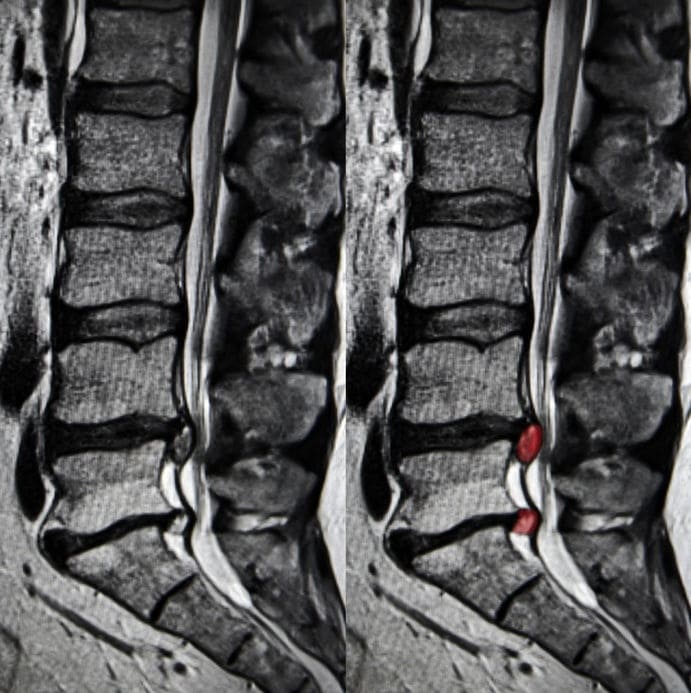

Как выглядит грыжа на МРТ

| МРТ снимок - грыжа поясничного отдела позвоночника | МРТ снимок - грыжа шейного отдела позвоночника | МРТ снимок - грыжа грудного отдела позвоночника |

![]() | ![]() | ![]() |

По причине более высокой нагрузки самыми частыми местами образования грыж являются позвонки L4 - L5 в области поясницы и L5 - S1. В ходе МРТ на сагиттальном срезе позвоночника при грыже врач-рентгенолог будет видеть четкое выбухание межпозвонкового диска. Будет видно, как часть пульпозного ядра из-за разрыва кольца вышла в спинномозговой канал. На МРТ-фото врачи смогут увидеть размеры грыжи, расположение, в какую сторону происходит выпячивание и степень давления на окружающие ткани.